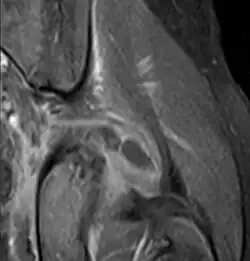

Transverse T2 magnetic resonance imaging section through the hip region showing abscess collection in a patient with pyomyositis.

Diagnostic methodDiagnostic method used for PM includes ultrasound, CT scan and MRI. Ultrasound can be helpful in showing muscular heterogeneity or a purulent collection but it is not useful during the first stage of the disease. CT scan can confirm the diagnosis before abscesses occur with enlargement of the involved muscles and hypodensity when abscess is present, terogenous attenuation and fluid collection with rim enhancement can be found. MRI is useful to assess PM and determine its localization and extension